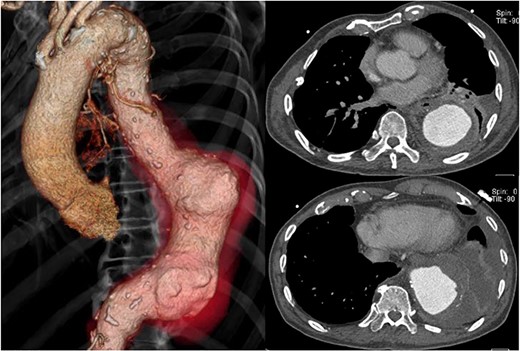

The patient had a fever (38°C) for 4 days after hospitalization, but his temperature dropped to 37°C afterward. His inflammatory reaction gradually improved, but CT angiography showed a descending aortic aneurysm, measuring 70 × 70 mm (Fig. 2). It extended 20 mm in only 2 weeks.

Preoperative CT shows acute expansion of the aneurysm to 70 mm in diameter.